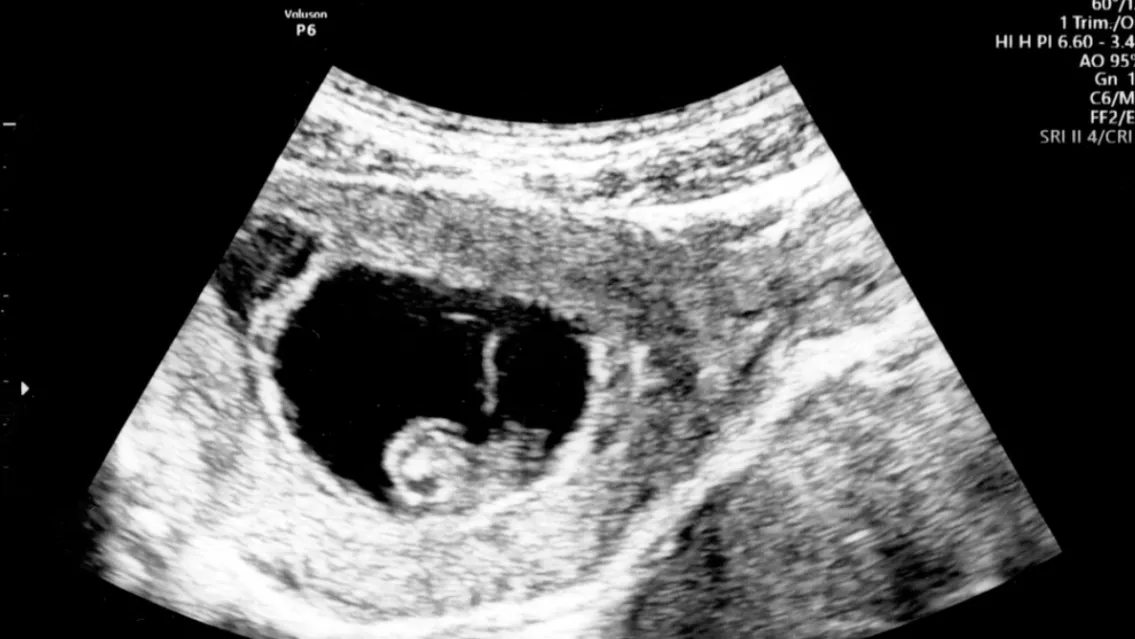

Además, sobre el presente de la mediática, señaló: "Está con Nicolás, él es un empresario, tiene supermercados mayoristas y un frigorífico". Y concluyó: "Está de tres meses y medio, y espera un varón".